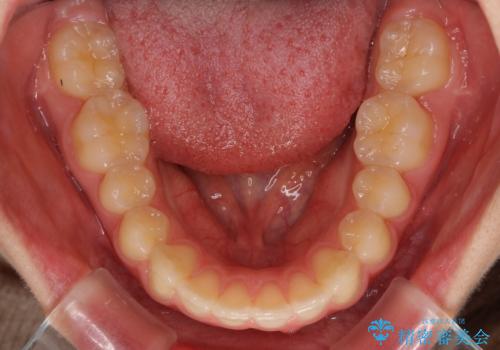

就職前にきれいな歯並びにしたい 大学生のインビザライン矯正

- 就職するまでに歯並びをきれいにしたいとのことで来院された患者様です。

前歯の叢生を気にしていましたが、極力突出感を改善できるようにすることとし、インビザラインにて矯正治療を行うこととしました。

改善の期待できない口元の突出感改善を希望されたため、いたずらに治療期間が延びましたが、きっちりと仕上がりました。